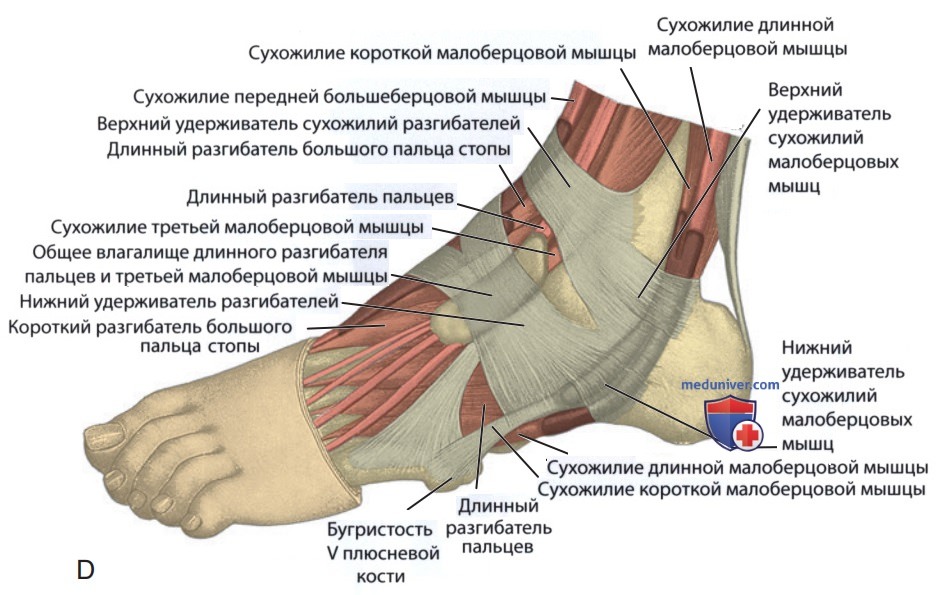

Анатомические фото голеностопного сустава и его суставных поверхностей